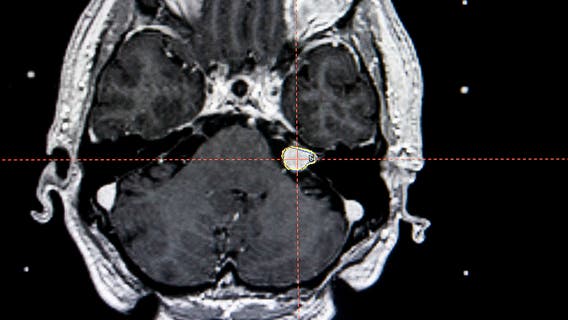

Radiation testing at Colonia High School amid brain cancer cluster

A medical mystery apparently links more than 100 people diagnosed with rare cancers to a New Jersey high school.

100 people with rare cancers who attended same NJ high school demand answers

By April 11, Al Lupiano had heard from more than 100 former Colonia High School attendees who had been diagnosed with rare cancers.